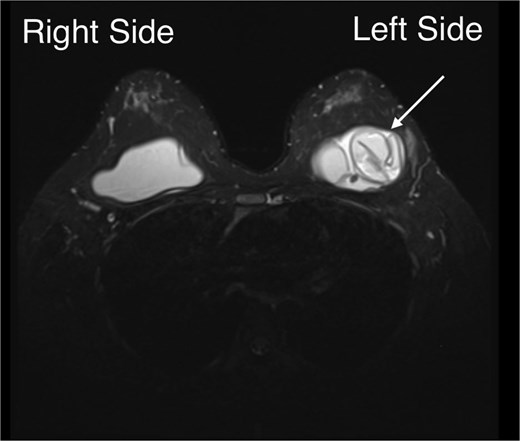

Examination showed mild breast asymmetry without focal tenderness, skin changes, or clinically apparent peri-implant fluid or palpable axillary lymphadenopathy. Capsular contracture was assessed as Baker grade I, with a soft, pliable capsule. Ultrasound showed normal breast parenchyma bilaterally without suspicious masses and no abnormal axillary lymph nodes. The left implant demonstrated findings interpreted as intracapsular rupture, without evidence of extracapsular silicone or peri-implant seroma; the right implant appeared intact (Fig. 1).

Diagnosis based on breast ultrasonography at 32 + 5 weeks’ gestation: We observed a multiloculated internal appearance (arrow), interpreted as intracapsular rupture, with no peri-implant seroma, extracapsular silicone, or regional lymphadenopathy; the right implant appeared intact.